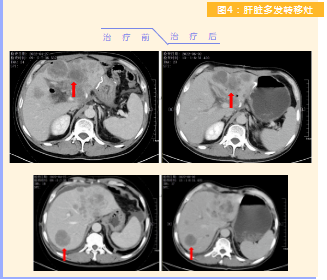

患者完成1周期治療后,上腹部疼痛癥狀基本消失,梗阻性黃疸癥狀緩解,腫瘤指標(biāo)下降(圖1),肺部多發(fā)轉(zhuǎn)移灶消失和縮?。▓D2),雙肺門淋巴結(jié)縮小(圖3),肝臟多發(fā)轉(zhuǎn)移灶縮小(圖4)。